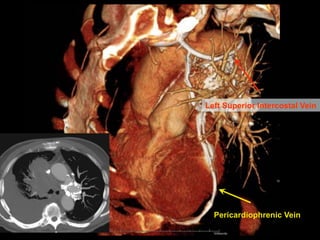

Left Superior Intercostal Vein

Pericardiophrenic Vein

Left Superior IntercostalVein Pericardiophrenic Vein